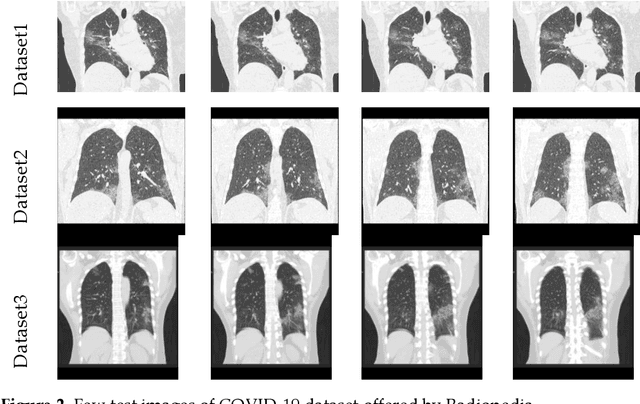

Abstract:Pneumonia is one of the foremost lung diseases and untreated pneumonia will lead to serious threats for all age groups. The proposed work aims to extract and evaluate the Coronavirus disease (COVID-19) caused pneumonia infection in lung using CT scans. We propose an image-assisted system to extract COVID-19 infected sections from lung CT scans (coronal view). It includes following steps: (i) Threshold filter to extract the lung region by eliminating possible artifacts; (ii) Image enhancement using Harmony-Search-Optimization and Otsu thresholding; (iii) Image segmentation to extract infected region(s); and (iv) Region-of-interest (ROI) extraction (features) from binary image to compute level of severity. The features that are extracted from ROI are then employed to identify the pixel ratio between the lung and infection sections to identify infection level of severity. The primary objective of the tool is to assist the pulmonologist not only to detect but also to help plan treatment process. As a consequence, for mass screening processing, it will help prevent diagnostic burden.